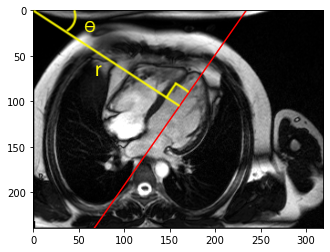

Parameter estimation